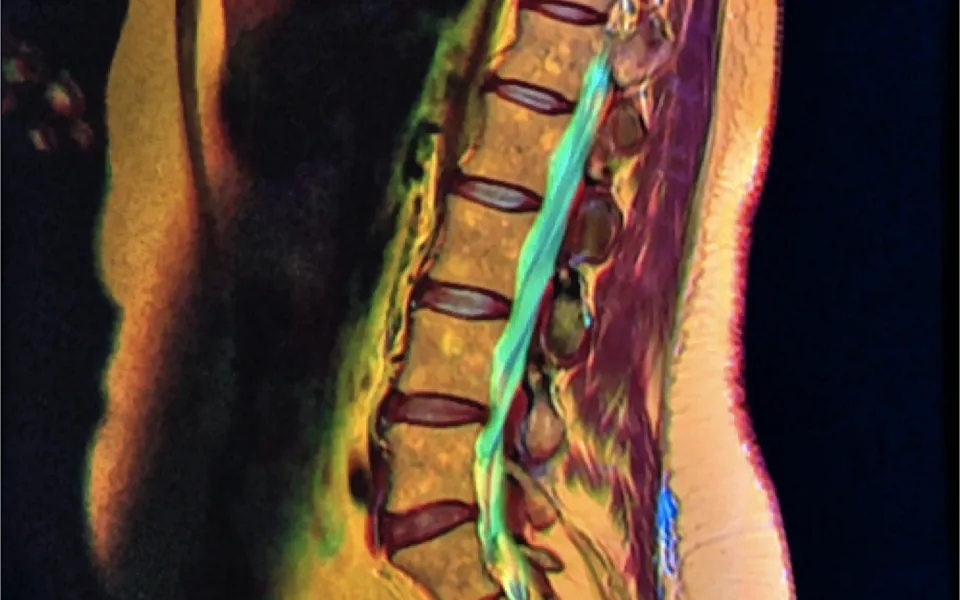

En un estudio publicado recientemente (Herzog, Elgort, Flanders, & Moley, 2017), la misma paciente, una mujer de 63 años, con historia de dolor lumbar y síntomas radiculares L5 en su miembro inferior derecho, visitó 10 centros de imagen diferentes en un periodo de 3 semanas. Los hallazgos de las resonancias magnéticas fueron comparados con un examen de referencia (dos de los autores revisaron los hallazgos de la resonancia magnética de forma independiente y establecieron un diagnóstico final por consenso).